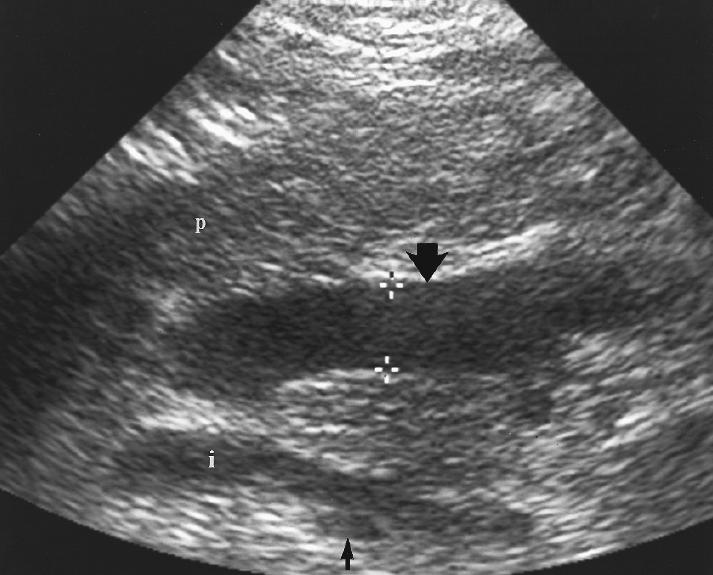

What is Portal venous hypertension?

This is an increase in portal venous pressure (above 10mmHg) or hepatic venous gradient (above 5mmHg).

What is the sonographic appearance of Portal venous hypertension?

Portal vein measures greater than 13mm

Collateral

circulation

Flow reversal

Ascites

Hepatosplenomegaly